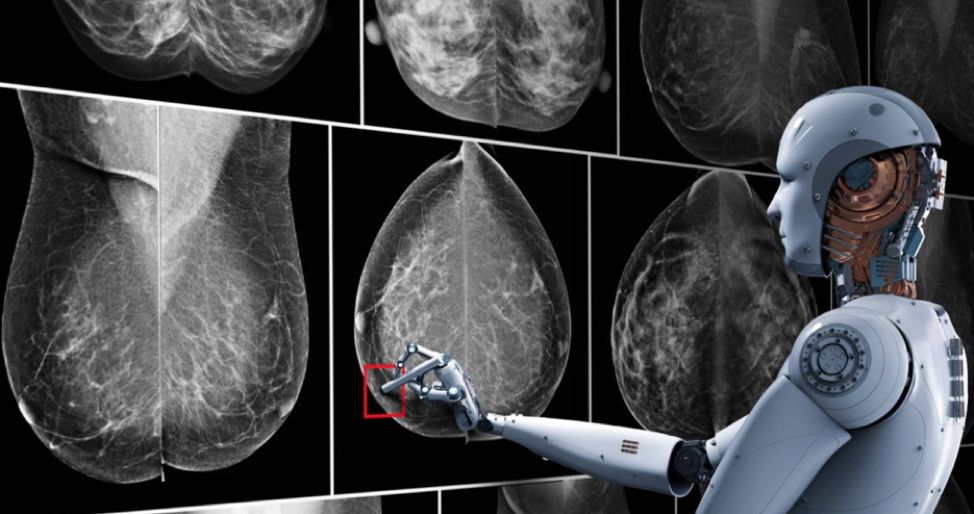

AI,会让放射科医生下岗吗?

然而,时至今日,智慧医疗最大的突破,仍然主要限于基于计算机视觉技术的医疗影像辅助诊断之上。AI,距离完全取代医生,可能还差了一个比邻星到地球的距离。

在这一情况之下,聚焦于最为成熟的医疗影像AI领域,谈谈AI在做什么,AI公司在做什么,可能显得更为重要。

计算机辅助诊疗技术(Computer Aided Diagnosis: CAD)借助机器视觉算法,对医疗影像进行自动分析,帮助医生锁定病灶,提供诊断建议和依据。传统上,基于人工设计规则的算法在功能、准确度和速度上均有较多局限。深度学习算法的引入,让CAD的应用场景大大扩展。从早期癌症筛查到心血管异常,从神经疾病诊断到骨骼肌肉损伤,CAD系统的AI化浪潮已是如火如荼。